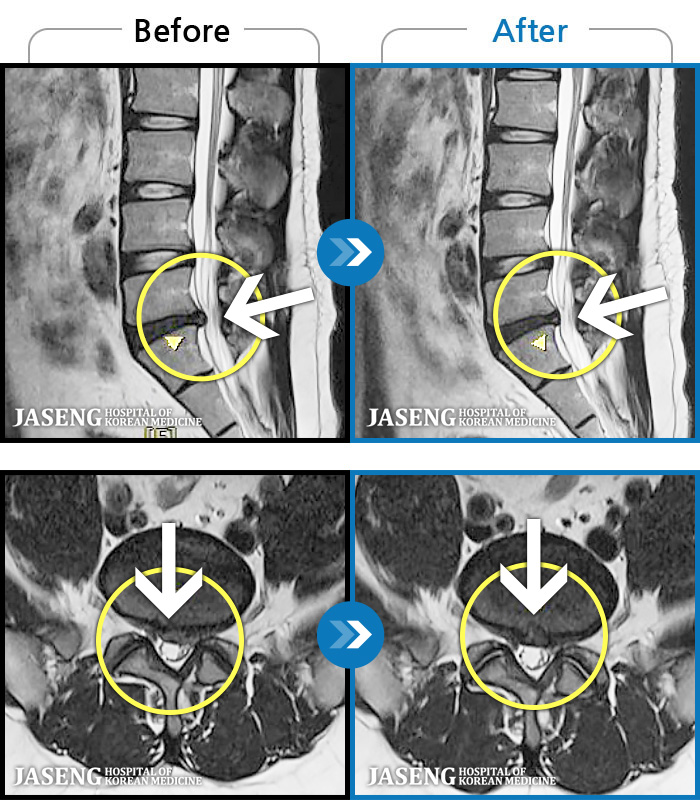

• 허리디스크